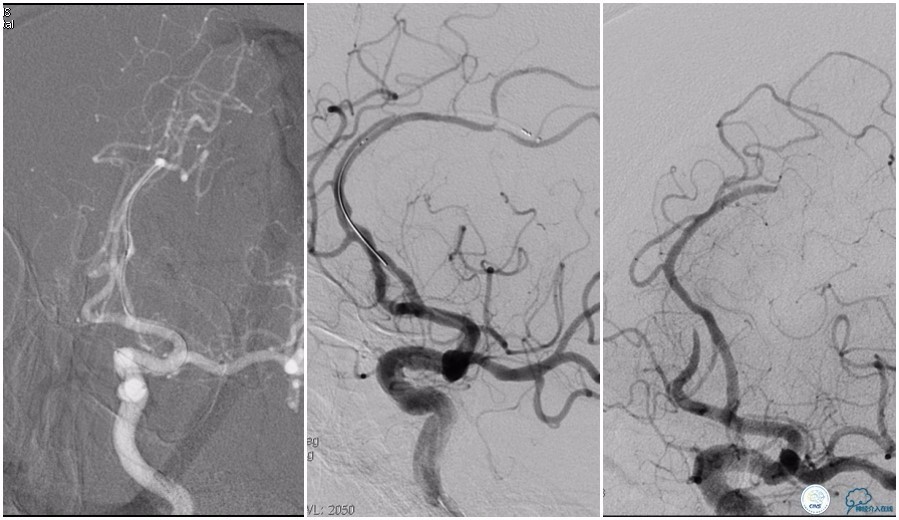

12:35穿刺成功,TOT 185min。3型主动脉弓,右侧颈内动脉起始部狭窄70%,右侧大脑前动脉A1段未显影。

双侧大脑前动脉A4段闭塞,右侧大脑前动脉由左侧大脑前动脉经前交通动脉代偿供血。

6F Envoy置于颈内动脉C3段,选用Solitaire-FR 4*20mm支架释放于右侧大脑前动脉,完全覆盖血栓。

6F Envoy置于左侧颈内动脉C3段,选用Solitaire-FR 4*20mm支架释放于右侧大脑前动脉取栓1次,血流达TICI 2b。

Solitaire-FR 4*20mm支架释放于左侧大脑前动脉取栓1次,取出少许血栓重复造影左侧大脑前动脉胼周动脉开口后,右侧大脑前动脉A2段以远未显影,考虑栓子逃逸。

选用Solitaire-FR 4*20mm支架分别于右侧大脑前动脉A2-A3段,左侧胼周动脉,右侧胼周动脉取栓3次。

双侧大脑前动脉完全显影,TICI 3级,TOR 261min。